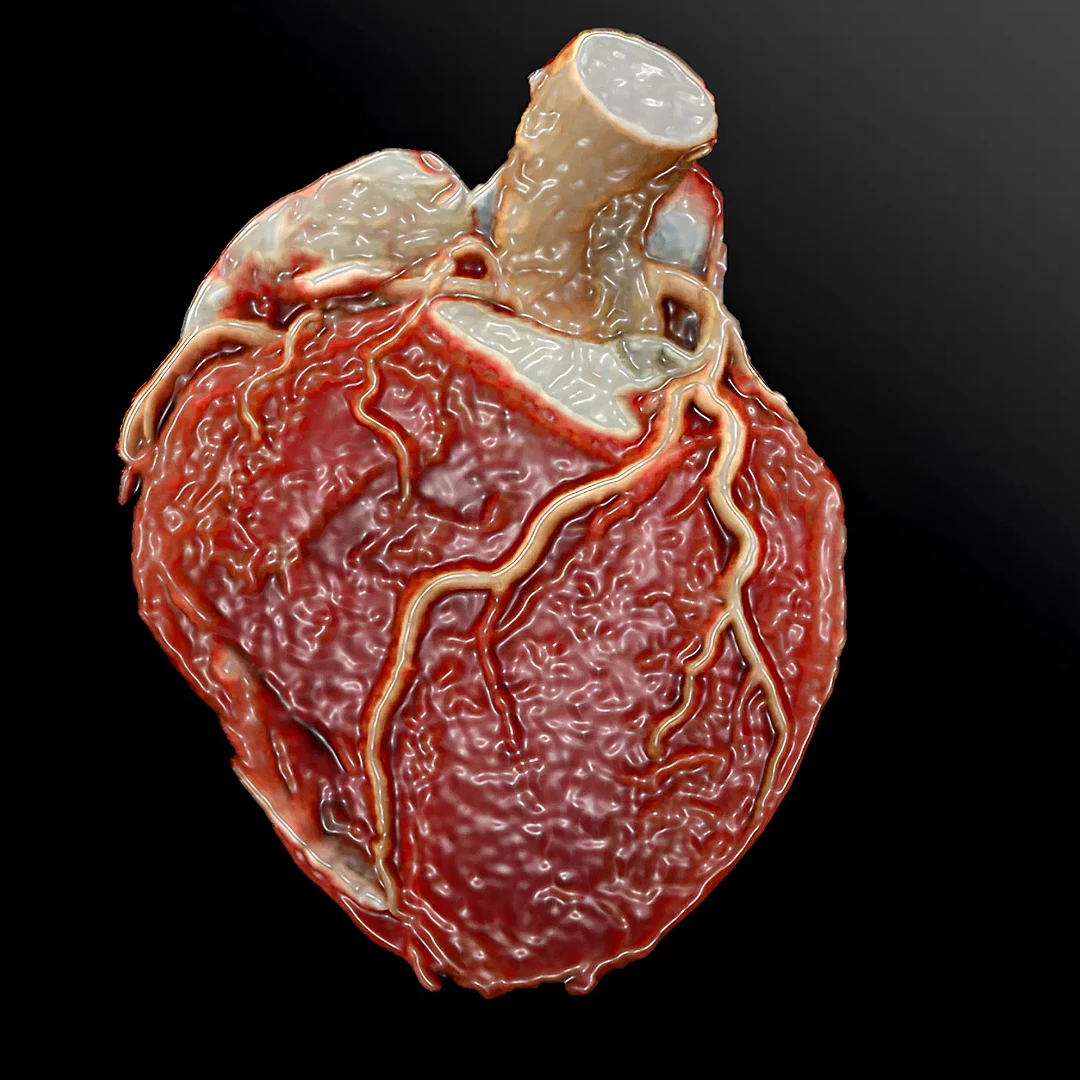

Adult and Congenital Cardiac CT provides detailed images of the heart’s structure and vessels to assess congenital defects, coronary artery disease, or other cardiac conditions. It’s a non-invasive tool offering precise insights for diagnosis and surgical planning.

Coronary Angiography CT

Calcium Score and Coronary Angiography CT evaluate plaque buildup and blood flow in the coronary arteries to assess heart disease risk. It’s a non-invasive, fast scan that helps detect early signs of coronary artery disease.